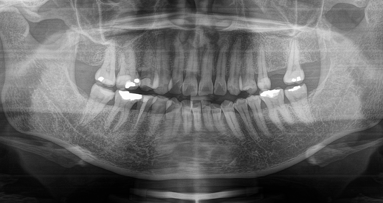

In the study, nineteen patients with severe periodontitis were randomised to receive standard periodontal treatment either alone or with a five-day course of an FMD. The study found that the FMD was safe and well tolerated and that it had only mild and temporary side effects, such as nausea, dizziness, weakness and fatigue.

While no statistically significant differences in systemic inflammatory markers were observed, three months after treatment, there was a trend towards a greater reduction in serum C-reactive protein in the FMD group compared with the controls. Additionally, a trend towards lower levels of key inflammatory biomarkers in the crevicular fluid was observed one day after treatment in FMD patients.